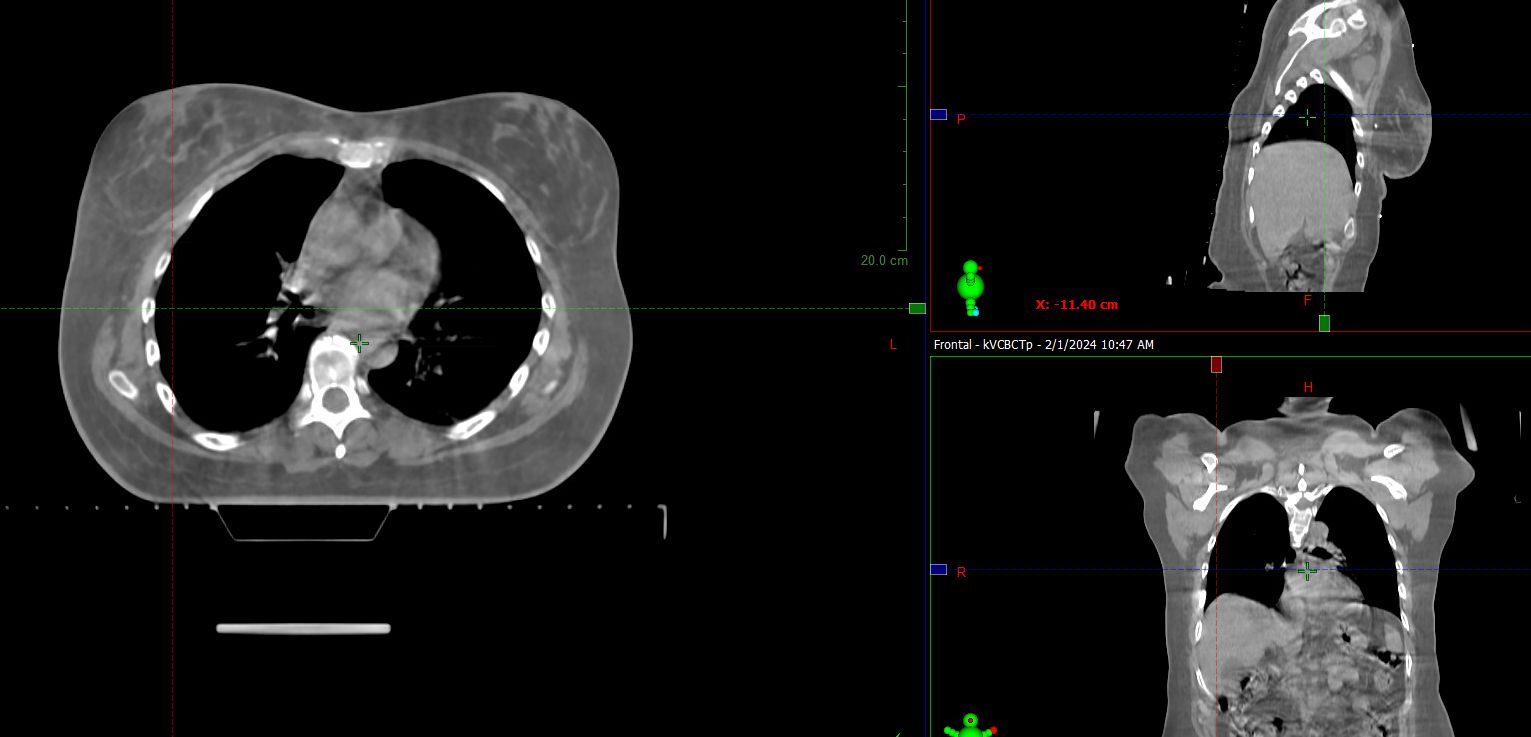

HyperSight brings fast, highly accurate imaging into the treatment room. It enables the acquisition of cone-beam CT (CBCT) images in as little as six seconds, with the Hounsfield Unit (HU) accuracy required for calculating dose distributions directly on the images. The HyperSight image reconstruction algorithms, combined with the expanded field of view (FOV) offer improved visualization of larger areas of interest often encompassing the entire target volume and surrounding organs at risk (OARs). HyperSight is now available as an optional feature on Varian’s Halcyon, Ethos, TrueBeam, and Edge radiotherapy systems.

According to Wesley Talcott, MD, MBA, radiation oncologist at Lenox Hill Hospital, HyperSight, and the high-resolution images it can generate, enable him to tighten margins and treat more challenging cases. “HyperSight allows us to potentially offer treatments to patients who may be more challenging to treat,” he says, citing the case of patients who would otherwise require very large margins that could increase toxicity, patients requiring a larger field of view, and abdominal patients with bilateral hip implants. “I don’t want to say that it would be impossible to treat these patients but treating with support from HyperSight imaging certainly gives us more confidence.” Because the high-fidelity imaging has the potential to make more treatment options available to physicians and patients, Dr. Talcott looks at HyperSight as an appealing differentiator in the Manhattan area.

HyperSight images show how radiotherapy treatment and physiological processes such as weight loss are impacting the tumor and surrounding anatomy over a course of treatment. The enhanced-quality HyperSight CBCT images generated right in the treatment vault make it possible to more easily compensate for any changes to the tumor and nearby organs. Previously, processes for adapting to such changes often required a new CT scan on a separate machine.

Clinicians at Icon Cancer Centre Holmesglen also use HyperSight imaging to streamline replanning decisions for patients on treatment. “When we see changes in volumes or contours, we are able to quickly run a calculation on the CBCT showing dose distributions for quicker decisions about whether to go ahead and treat or to stop and rescan,” says Sarah Hauville, Radiation Therapy Manager.